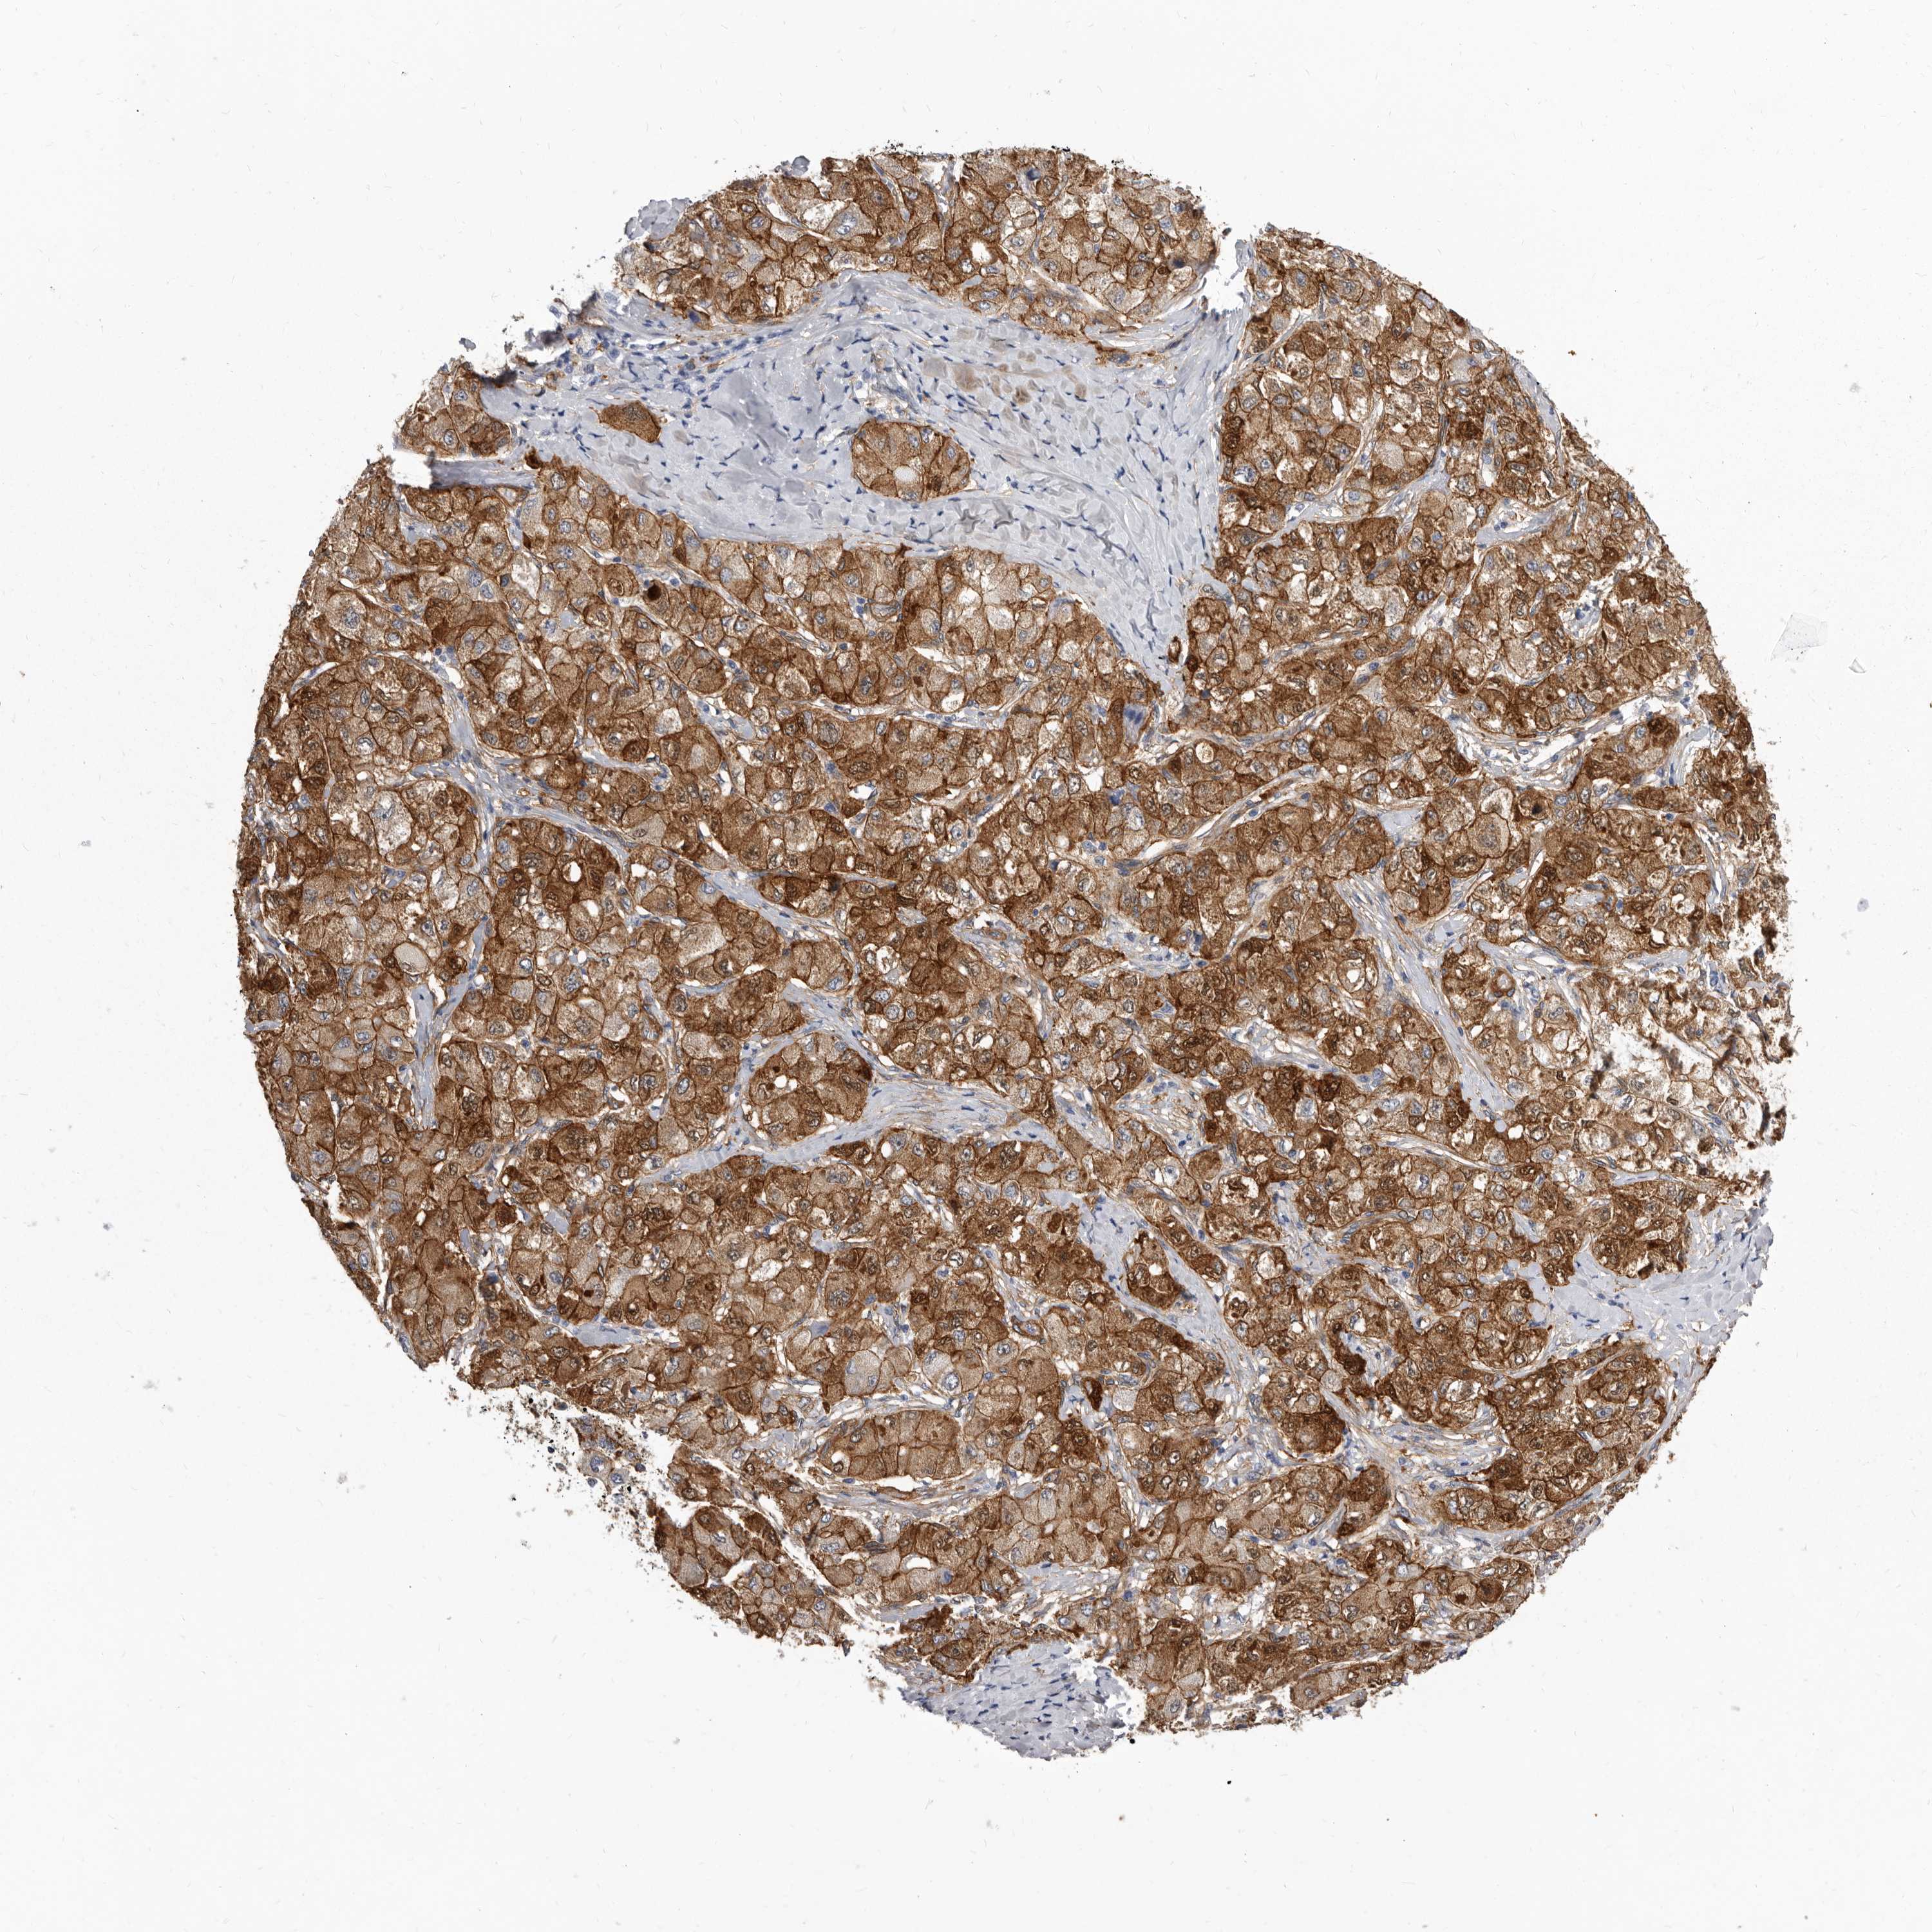

LIVER CANCER - Protein expressioni

A mouse-over function shows sample information and annotation data. Click on an image to view it in a full screen mode. Samples can be filtered based on level of antibody staining by selecting one or several of the following categories: high, medium, low and not detected. The assay and annotation is described here.

Antibody stainingi

Antibody staining in the annotated cell types in the current human tissue is reported as not detected, low, medium, or high, based on conventional immunohistochemistry profiling in selected tissues. This score is based on the combination of the staining intensity and fraction of stained cells.

Each image is clickable and will lead to virtual microscopy that enables deeper exploration of all samples and also displays staining intensity scores, fraction scores and subcellular localization as well as patient and tissue information for each sample.

Antibody HPA028448

Antibody HPA028696

Staining

High

Medium

Low

Not detected

Intensity

Strong

Moderate

Weak

Negative

Quantity

>75%

75%-25%

<25%

None

Location

Nuclear

Cytoplasmic/membranous

Cytoplasmic/membranous,nuclear

Cholangiocarcinoma

Carcinoma, Hepatocellular, NOS